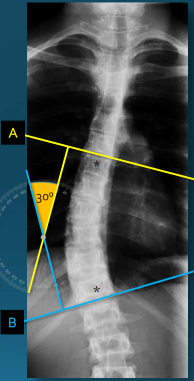

Q what is the name of this measurement? and what is the average + range?

A: Cobb's Method/ Cobb-Lippman method

assesses the degree of a spinal curvature (scoliosis). No average or range is specified as it is used to measure a pathology.

A: Risser-Ferguson Method